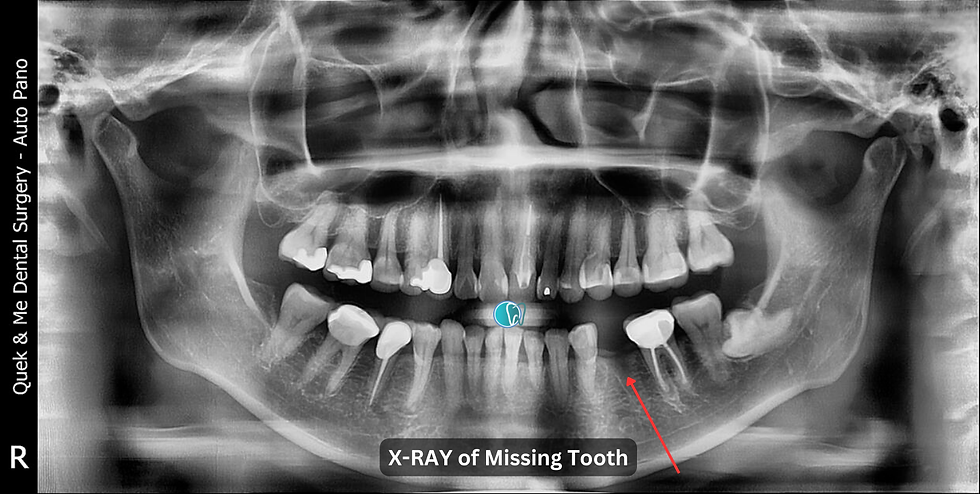

Replacement of missing tooth #35.

Placement of a dental implant at the site of missing tooth #35.